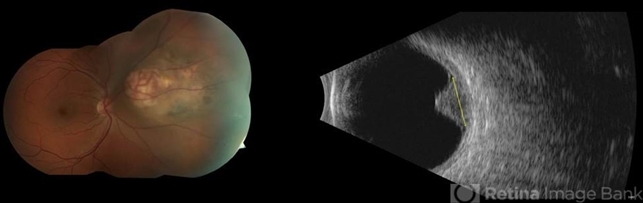

- juxtapapillary choroidal melanoma

- Fundus photograph and b-scan ultrasonographic image of a collar button choroidal melanoma with prominent intrinsic vascularity.